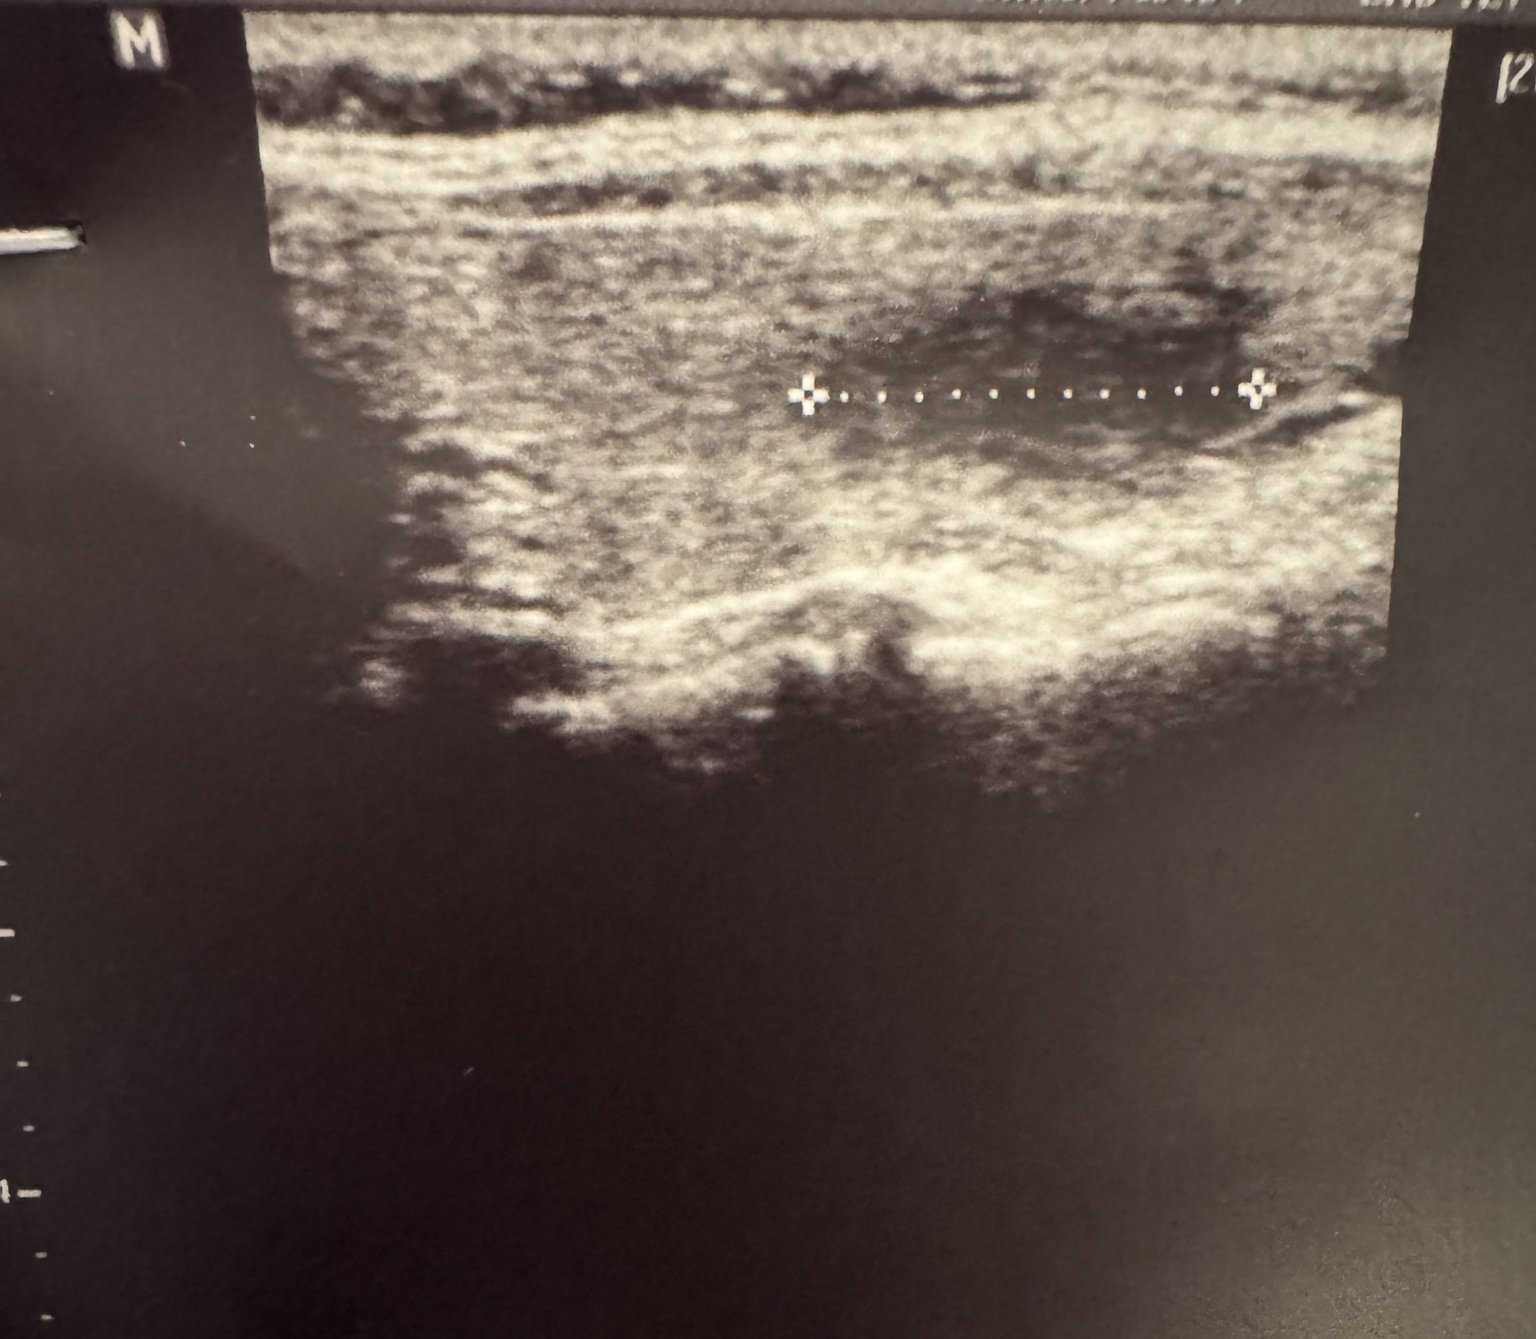

Какво може да означава нормалният, но нисък естрадиол в началото на цикъла при наличие на кисти?